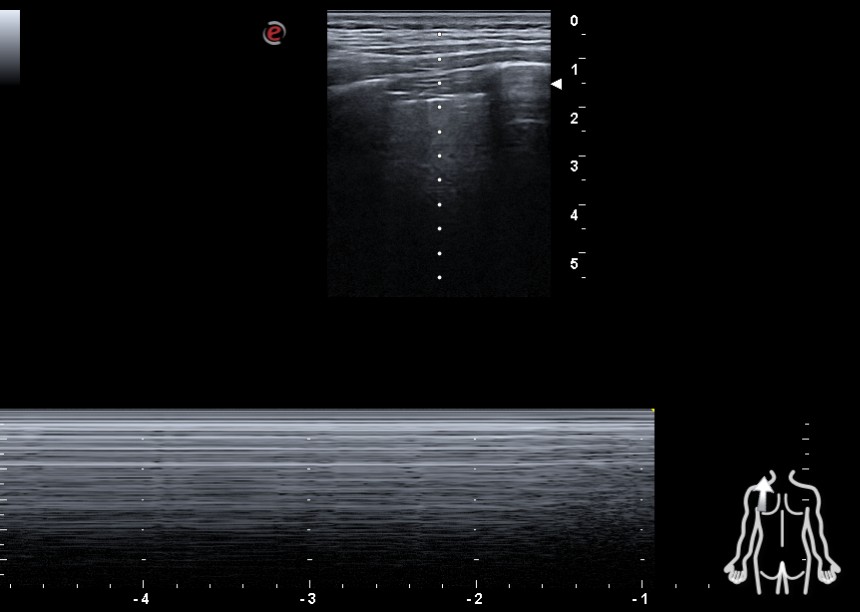

En región cervical y torácica bilateral, inferior a la fascia cervical, se observan puntos hiperecogénicos con artefacto en cola de cometa, compatibles con líneas “E”. En hemitórax izquierdo, ausencia de deslizamiento pleural y de líneas “B” y signo del código de barras, aunque no es posible visualizar el punto pulmomar.